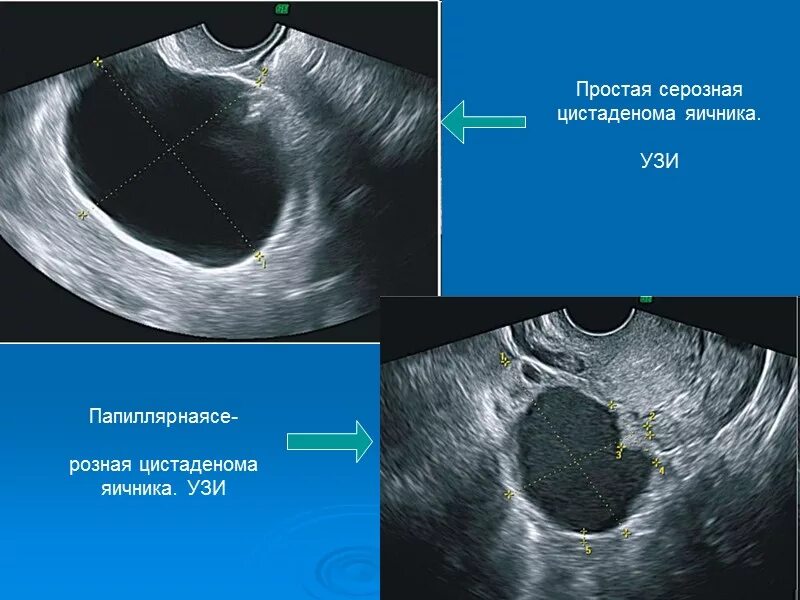

Объемные кистозные образования